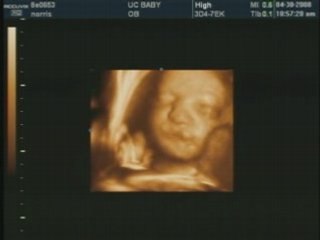

Ultrasound 3D 015

Fetal Studio offers affordable and professional access to prenatal ultrasound, limited medical surveys and level 1 ultrasounds, also the best 3D & 4D imaging quality available on the market.